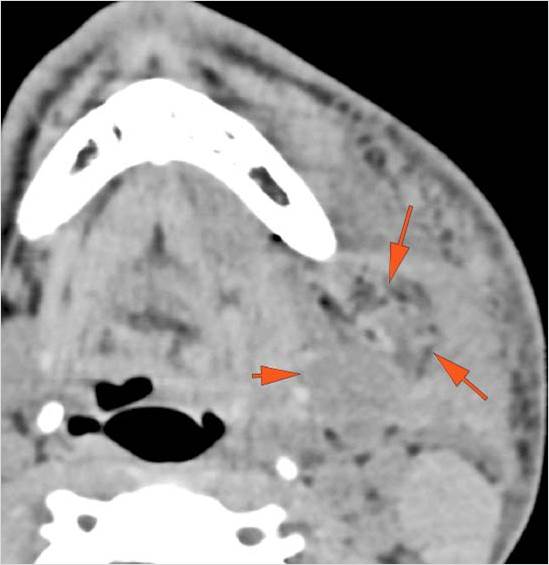

There is localized edema, hematoma or abscess within in the facial or scalp soft tissues, SMAS, infratemporal fossa, masticator space or oral cavity. [Yes/No]

There is evidence of gas or a foreign body at a possible fracture site, indicative of an open or penetrating injury. [Yes/No]

There is soft tissue swelling suggesting injury to the parotid or submandibular glands. [Yes/No]